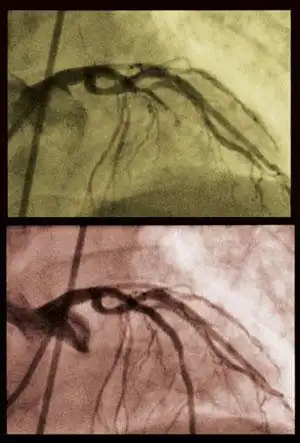

В конце 1960-х годов была впервые выполнена операция на коронарных артериях. С этого момента хирурги научились прокладывать обходные пути вокруг суженных участков мельчайших коронарных артерий, используя оптическое увеличение, очень тонкий шовный материал и методики, позволяющие работать на остановленном сердце.

Знаменитое аорто-коронарное шунтирование Ельцина, как раз является одной из видов операций на коронарных артериях...